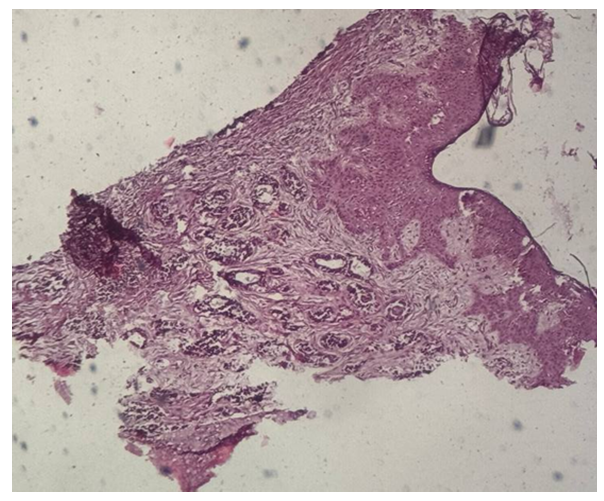

A total of 48 patients with salivary gland tumors were examined between 2023 and 2025. The cohort included 45 males and 3 females. The most frequent malignant neoplasms were undifferentiated carcinoma (4 cases) and adenocarcinoma, stage I (3 cases). Benign tumors included pleomorphic adenoma (1 case) and monomorphic adenoma (1 case).Histopathological examination revealed distinct morphological patterns characteristic of each tumor type. Representative photomicrographs are presented below. | Figure 1. Undifferentiated carcinoma (H&E stain, ×10) |

Morphological description: Tumor tissue demonstrates a solid growth pattern with sheets of atypical epithelial cells. The cells show high nuclear-cytoplasmic ratio, hyperchromatic nuclei, and loss of normal glandular architecture. Areas of necrosis and irregular stromal infiltration are evident. No clear glandular or squamous differentiation is observed, which corresponds to the diagnosis of undifferentiated carcinoma. Figure 1. Histological section of undifferentiated carcinoma of the salivary gland showing solid sheets of atypical cells with hyperchromatic nuclei and absence of glandular differentiation (H&E stain, ×10). | Figure 2. Undifferentiated carcinoma (mandibular localization, H&E stain, ×10) |

Morphological description: The histological section demonstrates infiltrative tumor growth with dense sheets of atypical epithelial cells. Cells display pleomorphism, irregular nuclear contours, hyperchromasia, and scant cytoplasm. The stroma is fibrous, with focal desmoplastic reaction. No signs of glandular or squamous differentiation are present, which is consistent with the diagnosis of undifferentiated carcinoma of the mandible. Figure 2. Undifferentiated carcinoma of the mandible showing sheets of pleomorphic tumor cells with hyperchromatic nuclei and fibrous stromal reaction. No evidence of glandular or squamous differentiation is observed (H&E stain, ×10). | Figure 3. Monomorphic adenoma (left submandibular gland, H&E stain, ×20) |